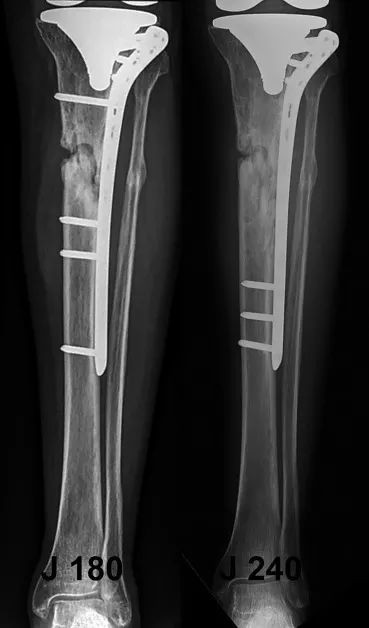

Обеспечивая, чтобы конструкция не была слишком жесткой из-за недостаточной рабочей длины фиксирующей пластины или чрезмерного количества фиксирующих гвоздей (рис. 7), можно снизить риск поломки фиксирующей пластины ниже отверстий для винтов или в месте соединения винт/костная пластина.

Рисунок 7. Заживление кости было достигнуто через 60 дней за счет изменения количества и положения стопорных винтов и увеличения эластичности чрезмерно жестких структур.